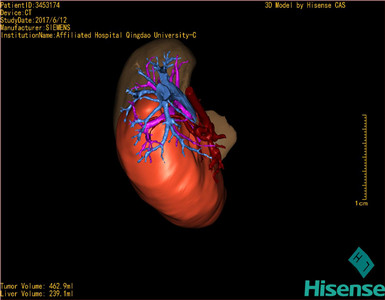

将0.625mm双源薄层CT资料的静脉期和动脉期Dicom格式文件导入海信CAS系统。

通过调节窗宽窗位调整CT序号,对肝实质,胆囊,下腔静脉,肿瘤,肝动脉、门静脉及肝静脉等进行三维重建;系统自动计算肝脏体积。

模拟手术操作,自动计算切除肿瘤体积。肝脏体积为310.9ml,肿瘤体积为437.7ml,肿瘤体积是肝体积的1.4倍,通过比对9-12月正常肝脏体积为321.13±118.91ml,通过术前模拟手术,精准判断切除后剩余肝脏体积能耐受,避免肝衰竭发生。

术前三维重建:

重建图片